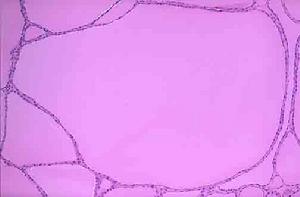

甲狀腺的大體檢查多呈瀰漫性腫大,質地堅韌或橡皮樣,表面呈結節狀,邊緣清,包膜完整,無粘連。鏡檢可見病變甲狀腺組織中淋巴細胞和漿細胞呈彌散性浸潤。腺體破壞後,一方面代償地形成新的濾泡,另一方面破壞的腺體又起刺激免疫作用,促進淋巴細胞的增殖,因而在甲狀腺形成具有生髮中心的淋巴濾泡。甲狀腺上皮細胞出現不同階段的形態,早期有部分濾泡增生,濾泡腔內膠質多;隨著病變的進展,濾泡變小和萎縮,腔內膠質減少,其上皮細胞腫脹增大,胞漿呈明顯的嗜酸染色反應,稱為Askanazy細胞或Hürthle細胞,進而細胞失去正常形態,濾泡結構破壞,間質有纖維組織增生,並形成間隔,包膜常無病變累及。